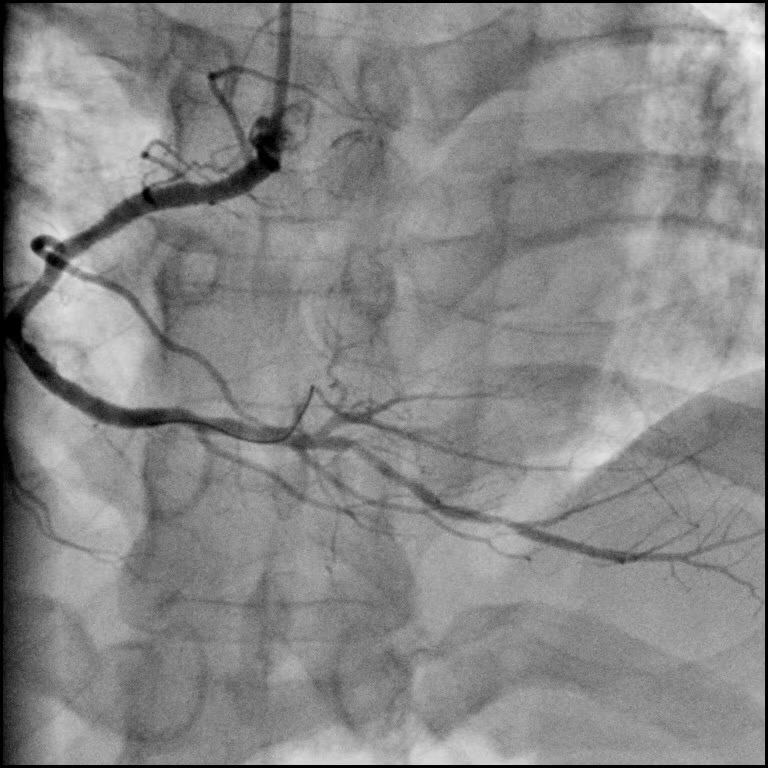

冠脈造影(唯邁醫(yī)療極光平板DSA)